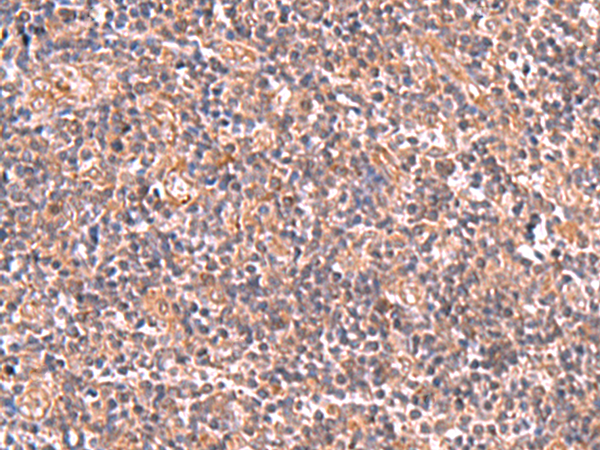

分类: 科研抗体货号: P10149别名: FPS; FPPS; POROK9应用: IHC反应种属: Human, Mouse, Rat